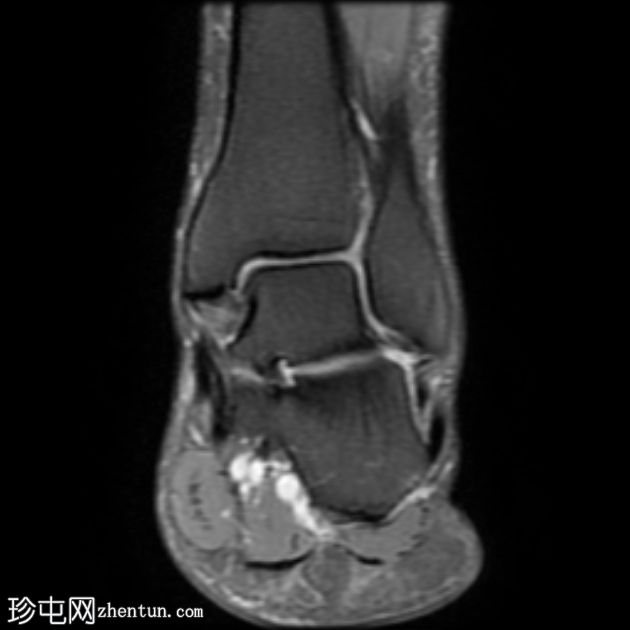

MRI

冠状位

梯度回波

跟腱插入

,伴有跟腱明显增厚,可诱发异常信号、跟腱后滑囊炎、跟骨后突及骨髓水肿信号。

Haglund综合征的检查结果令人印象深刻。

Haglund综合征是指以下三联征(Haglund三联征):

跟腱插入性病

跟腱后滑囊炎

Haglund畸形(即跟骨后上外生骨疣)